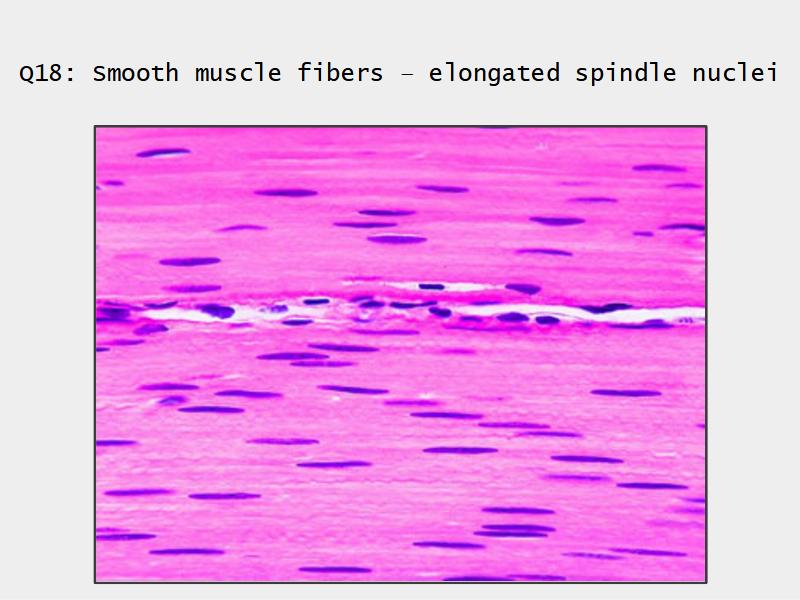

- Smooth muscle REPLACE cartilage

- Smooth muscle